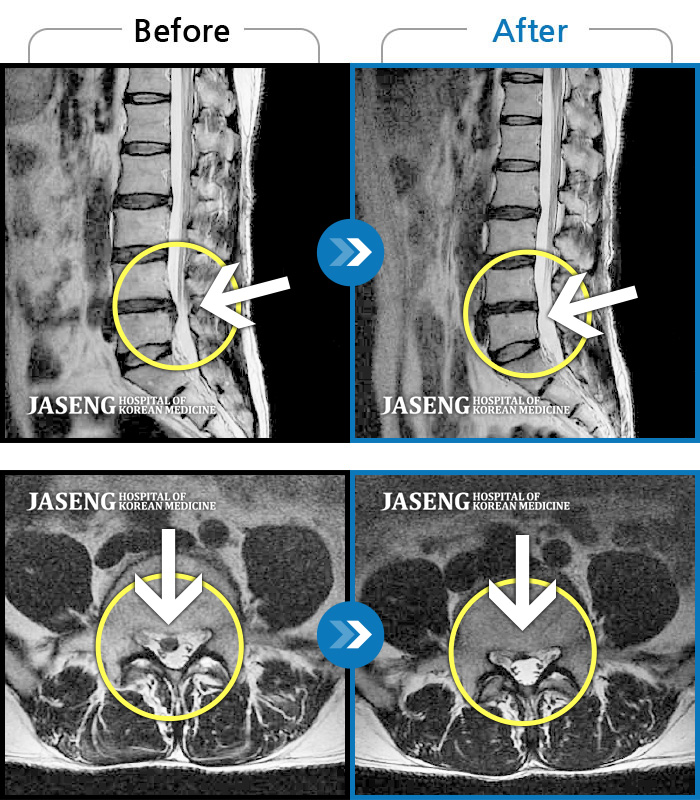

허리디스크

수원 · 김태성 원장

허리 통증과 좌측 대퇴부~종아리 저림과 통증

촬영시기

2011.03.14 ~ 2024.05.24

2024.11.21